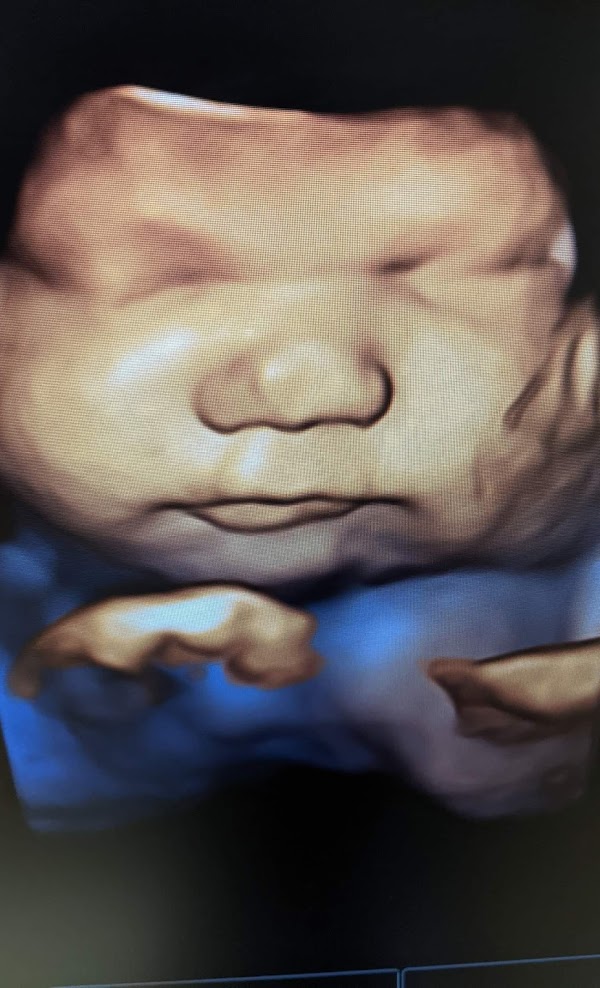

Sweet Baby Face Elizabethtown 120 Drexler Cir Elizabethtown KY 42701. 3D 4D Ultrasound in Elizabethtown Ky.

. Gender as early as 8 weeks. Sweet baby face is the premier facility for elective HD 3d4d Ultrasounds in. Sweet baby face offers 3d 4 d Ultrasound in Louisville and.

Get directions reviews and information for Sweet Baby Face in Elizabethtown KY. Sweet Baby Face hd 3d 4d ultrasound. Medical Center in Elizabethtown.

Ultrasound Clinic Gallery See Louisville Elizabethtown Babies